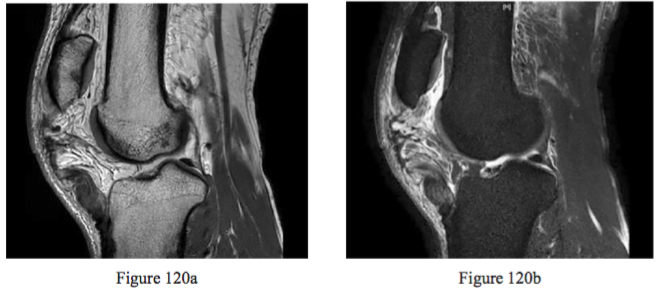

Question 120

Figures 120a and 120b are the sagittal MR images of a man who injured his knee after he slipped and fell

on ice 2 days ago. He has severe knee pain and instability. Examination is di cult because of swelling, guarding, and apprehension. What is the indicated treatment?